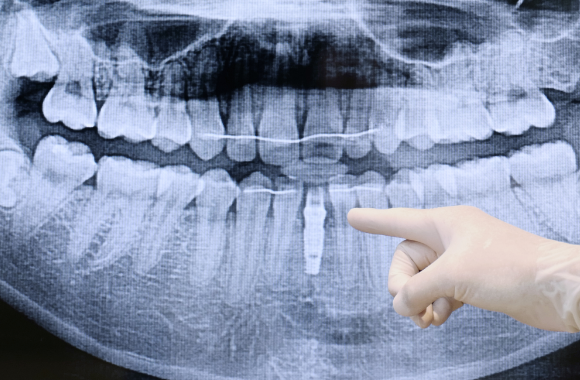

R2 게이트

임플란트 수술 전 3D 컴퓨터 진단 및 가상 모의 수술 시스템으로써 수술 진행 시 임플란트의 위치를 미리 파악할 수 있으며 수술 중 발생할 수 있는 신경 손상 등 사전 위험 요소를 차단하는 시스템입니다.

저희 목포미르치과병원에서는 구강 스캐너와 디지털 기공실을 원내에 두고 있어 디지털 기술을 활용하여 더욱 정밀하고 명확한 임플란트 치료를 진행하고 있습니다.

• 01

정밀진단

3D 모의 수술을 위해 첨단 장비를 이용하여 환자의 구강 상태, 뼈, 신경의 위치 등의 검사를 진행합니다.

• 02

치료 계획

검사 결과를 바탕으로 임플란트 수술 가능 여부와 치료 계획에 대해 심도 있는 상담을 진행합니다.

• 03

3D 모의 수술 진행

환자의 구강 상태에 맞는 최적의 식립 각도와 길이를 측정하여 수술의 완성도를 높이기 위해 3D 모의 수술을 진행합니다.

• 04

가이드 제작

모의 수술 결과를 토대로 환자의 구강 상태에 맞는 임플란트 수술 가이드를 제작합니다.

• 05

임플란트 수술

3D 모의 수술한 결과를 토대로 제작된 가이드 장착 후 환자에게 적합한 식립 각도와 수술 경로를 통해 수술을 진행합니다.